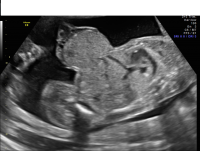

Omphalocele

Omphalocele is a type of “ventral wall defect” which is diagnosed when some of the organs of the abdomen protrude through an opening in the abdominal muscles near the umbilical cord insertion into the body. These organs are covered by a clear sac or membrane. Small omphaloceles are seen in one out of every 5,000 newborns, whereas giant omphaloceles are less common, and occur in one of every 10,000 newborns.

Omphalocele axial view